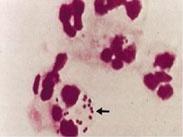

• 肺炎球菌肺炎

628健康網為您分享有關肺炎球菌肺炎的癥狀,肺炎球菌肺炎的治療方法,肺炎球菌肺炎的預防知識,肺炎球菌肺炎的癥狀圖片,肺...